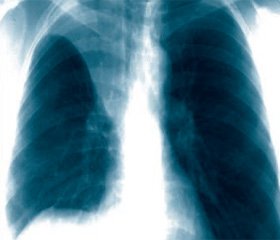

Помимо опроса и объективного осмотра, включающего перкуссию и аускультацию грудной клетки, проводят рентгенологическое исследование в двух положениях тела (в 2-х проекциях). Это основной метод обнаружения ателектазов легких.

На рентгеновских снимках выявляют следующие признаки, указывающие на спадение легочной ткани:

Однородное затемнение в области поражения. Размеры тени зависят от вида ателектаза: при долевом выявляется обширное затемнение, при сегментарном — в виде клина или треугольника, расположенного вершиной к корню легкого, дольковые ателектазы множественные и похожи на очаговую пневмонию. Дистензионный ателектаз расположен низко, около диафрагмы, имеет небольшие размеры и вид поперечных полос или темных дисков. Смещение органов: при компрессионном ателектазе смещение наблюдается в здоровую сторону, так как на стороне поражения давление больше, при обтурационном, наоборот – смещение будет в сторону ателектаза, так как на стороне поражения нарастает притягивающее отрицательное давление. Подъем купола диафрагмы – это видно по расположению печени.

Помимо всего перечисленного выше, рентгеноскопия, то есть исследование «вживую», позволяет увидеть куда смещаются органы в зависимости от фазы дыхания, кашля. Это является дополнительным признаком ателектаза, помогающим выявить тип болезни.

Предварительным, рентгенологическим диагнозом является «синдром правой доли», при котором выявляется затемнение площади средней доли правого легкого.

Частое возникновение ателектаза правого легкого связано с анатомическими особенностями правого среднедолевого бронха: он узкий и длинный, поэтому часто происходит его перекрытие при патологическом процессе.